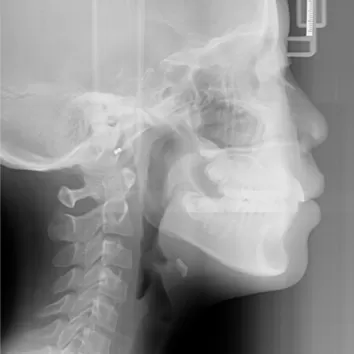

X-rays before treatment

[Panoramic Radiography/Lateral Cephalogram]